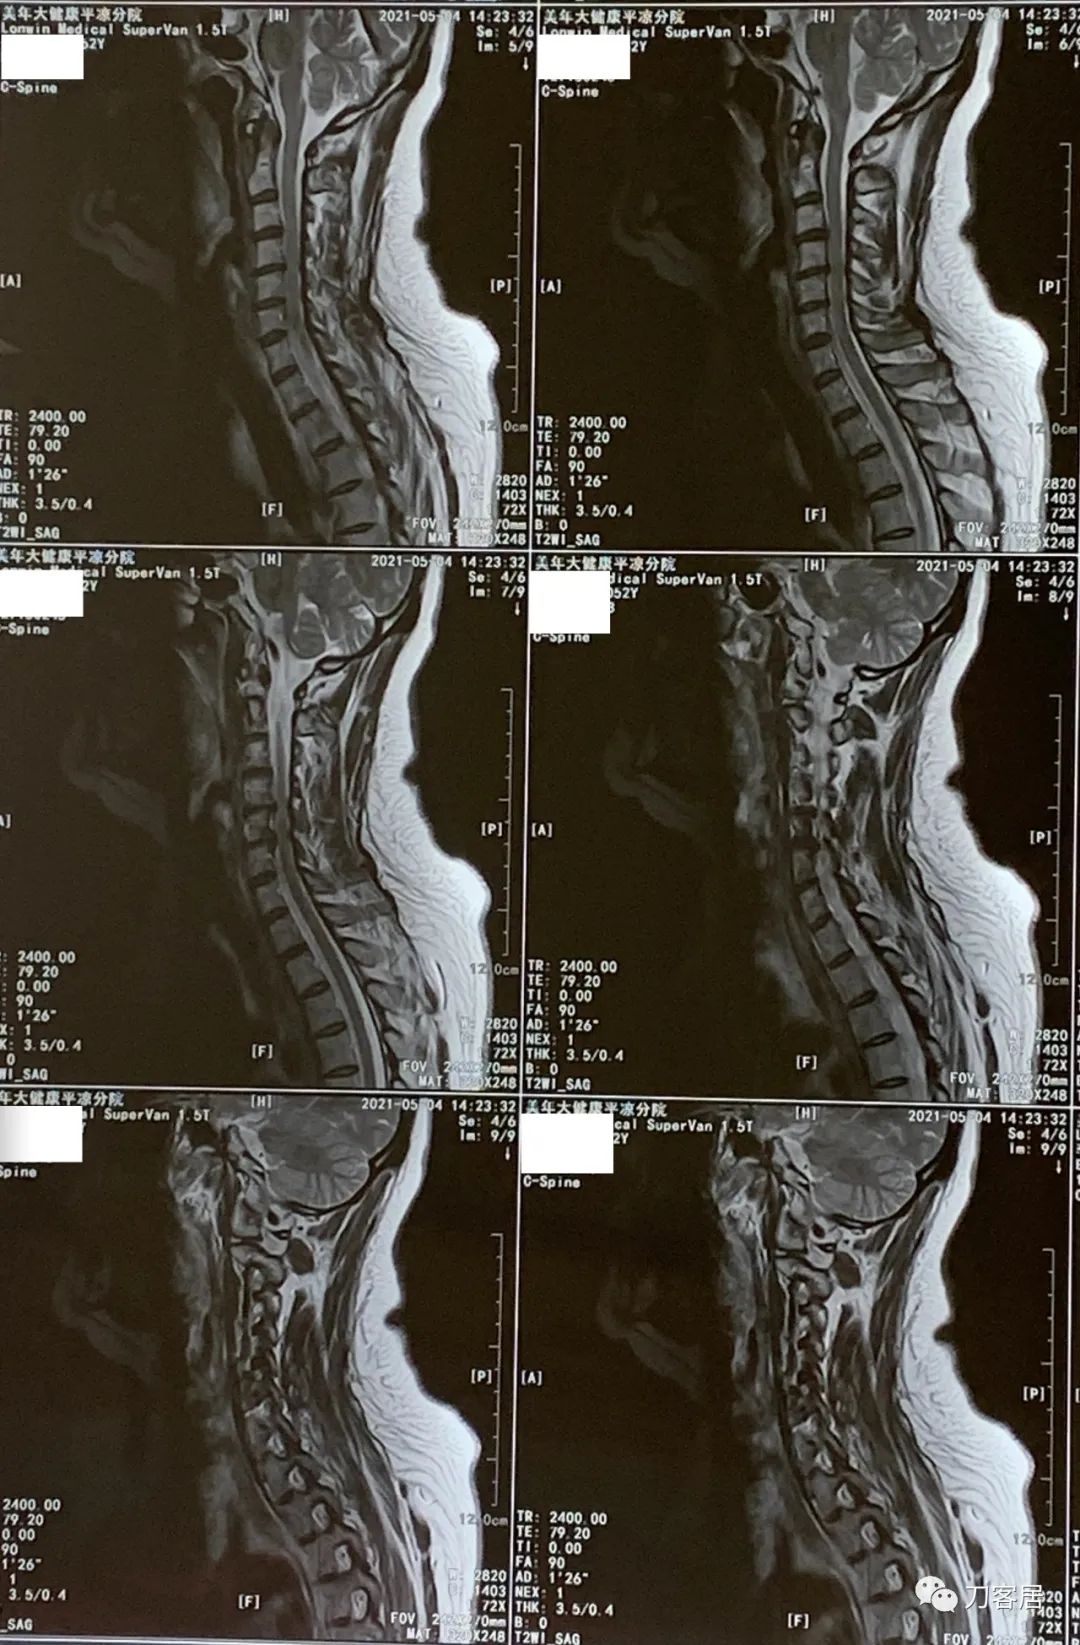

患者回当地后,一直没有再去医院就诊,不过到了2021年5月4日,患者在当地又做了一次颈椎磁共振检查。也就是经过抗骨质疏松治疗后,患者的临床症状应该都没了,恢复了正常的生活,从2020年8月19日到2021年5月4日,将近9个月,患者没有再去医院看病,到了2021年5月4日,患者又做颈椎磁共振,应该是患者自行停药,颈肩痛的症状又来了,然后到当地医院就诊,仍然考虑颈椎病,给开了颈椎磁共振检查。

图22. 20210504美年大健康平凉分院颈椎MRI01

图23. 20210504美年大健康平凉分院颈椎MRI02

图24. 20210504美年大健康平凉分院颈椎MRI03

图25. 20210504美年大健康平凉分院颈椎MRI04

图26. 20210504美年大健康平凉医院颈椎MRI报告